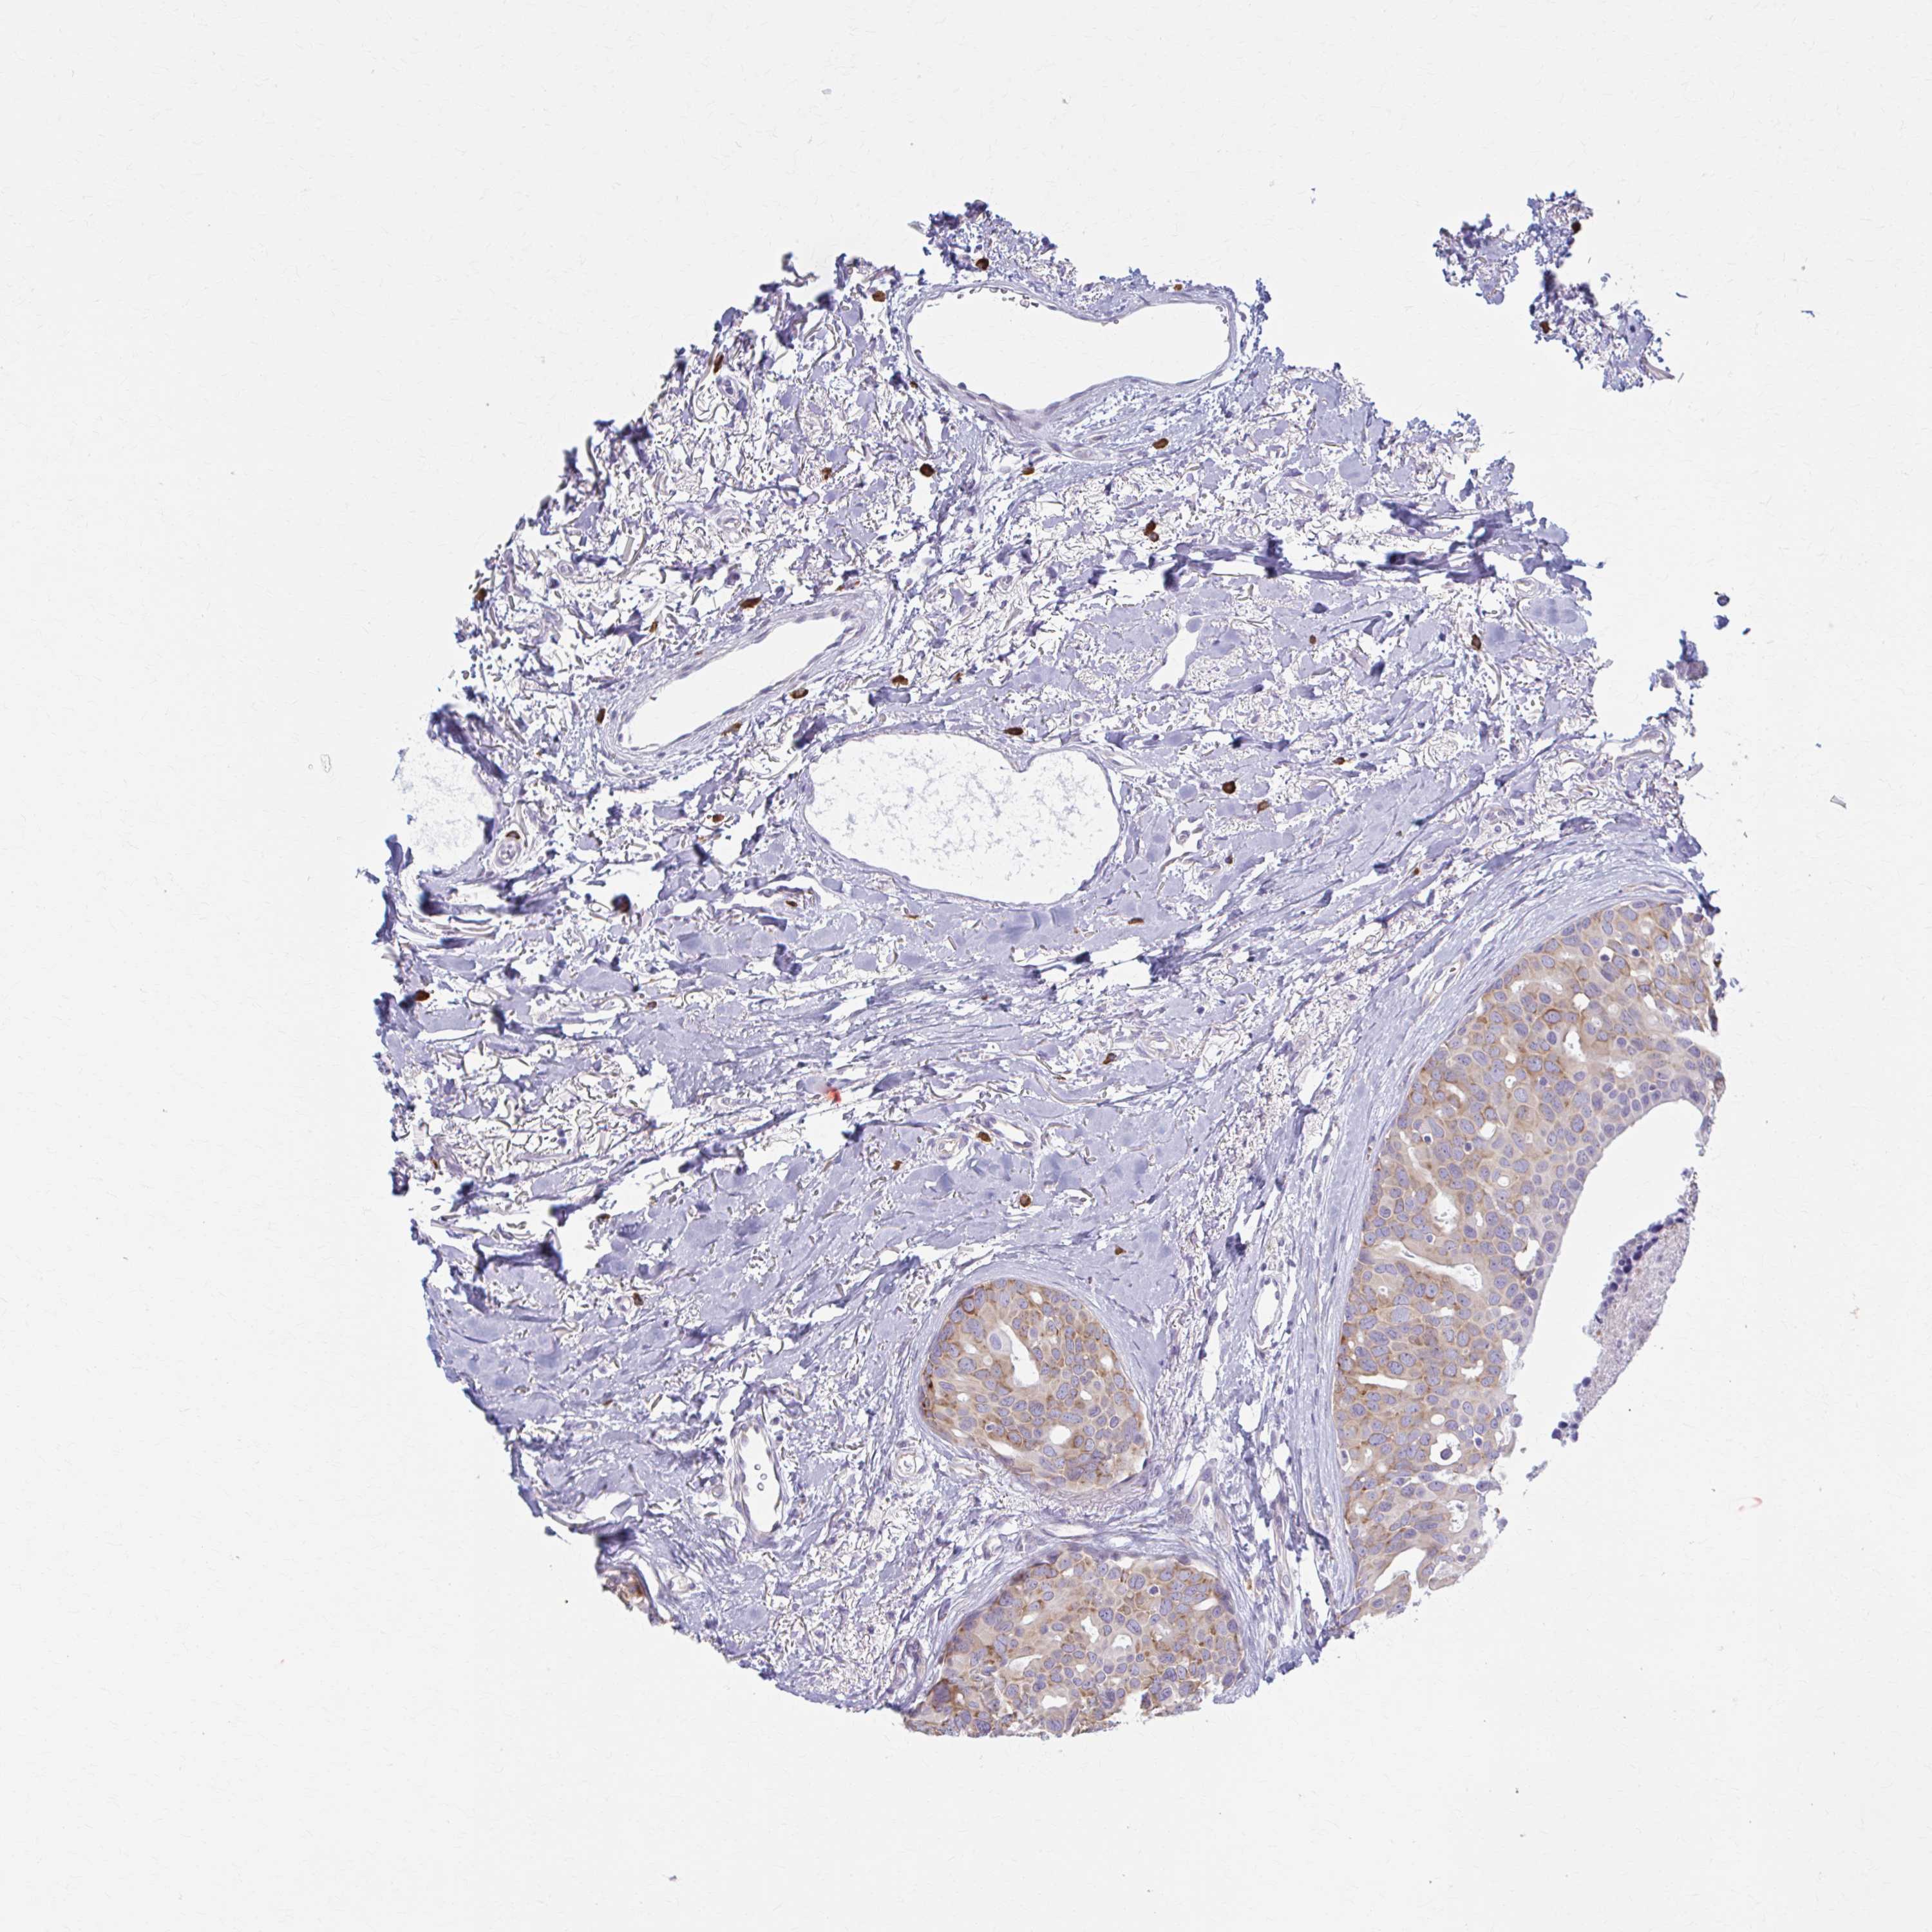

CANCER BREAST CANCER Show tissue menu

BRCA TCGA BRCA VALIDATION PROTEIN EXPRESSION

Breast cancer

Human cancer